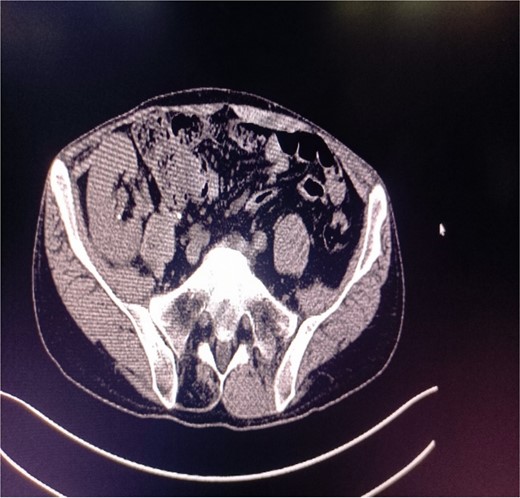

Abdominal CT showing multiple punctate stones in the right renal area in situ.

A 39-year-old man with kidney stones after kidney transplantation was admitted to our hospital on 29 November 2023. Eight years ago, he underwent a kidney transplant from a donor. Neither the donor nor the recipient had a history of kidney stones. The transplanted kidney was positioned in the right iliac fossa, and the patient had a successful postoperative recovery. However, a recent routine abdominal computed tomography (CT) scan revealed multiple stones in the transplanted kidney and bilateral in situ kidney atrophy. The stone was located in the lower calyx of the transplanted kidneys. Hydronephrosis was also observed. Kidney, ureter, and bladder radiographs showed multiple high-density speckles in the right kidney, the largest of which was ~0.5 cm in diameter. Physical examination (blood pressure, 147/91 mmHg; serum creatinine, 72.7 μmol/L; urea nitrogen, 5.1 mmol/L) revealed normal liver function, coagulation, and electrolytes. We suspected that these kidney stones were sizable and necessitated surgical intervention. Upon admission, pertinent examinations were conducted, and preoperative preparations were completed.